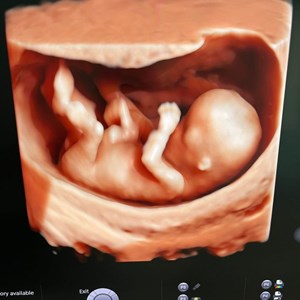

Når en 3D scanning bliver en magisk lille stund for den ventende familie 💞 Denne lille p...